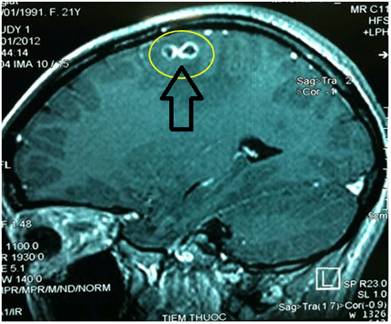

Toxocara canis và Toxocara cati là các loài giun tròn thuộc họ Ascaridae, trong đó các giai đoạn trưởng thành hay ký sinh sinh ở ruột non của các động vật có vú và các con vật này đóng vai trò là các vật chủ xác định thuộc chó và mèo. Toxocara canis hoàn thành chu kỳ trên chó, người mắc phải như một vật chủ tình cờ, nhiễm do nuốt phải trứng nhiễm trong môi trường đất bị ô nhiễm. Sau khi nuốt vào, trứng nở thành ấu trùng đi xuyên qua thành ruột và di chuyển khắp hệ tuần hoàn qua các mô (gan, tim, phổi, não, cơ, mắt), nhiều ca bệnh chuyển nặng, đe dọa tính mạng, thậm chí tử vong do chẩn đoán nhầm, phát hiện muộn và điều trị không hợp lý. Mặc dù các ấu trùng không phát triển thêm trong các cơ quan này, song chúng gây ra một số phản ứng tại chỗ - chính là các “vấn đề” của bệnh giun đũa chó, mèo.

Hai thể lâm sàng chính của bệnh ấu trùng giun đũa chó là ấu trùng di chuyển nội tạng (visceral larva migrans-VLMs) và ấu trùng di chuyển ở mắt (ocular larva migrans-OLMs). Các triệu chứng khác gồm có sốt, ho, khò khè, mày đay, ngứa, chán ăn, gan lớn và tăng bạch cầu ái toan nhất là trên các thể thông thường gặp (covert toxocariasis-CTs). Các triệu chứng trên thường cũng xuất hiện trên các bệnh nhân nhiễm trùng các ký sinh trùng và đơn bào khác, hoặc dễ nhầm với một số bệnh nội khoa, truyền nhiễm hoặc da liễu, nên việc đưa ra khung chẩn đoán thống nhất là rất cần thiết hiện nay.